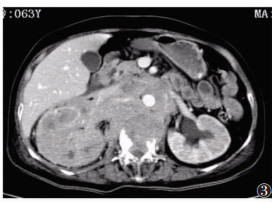

| 图 1 女,64岁 CT平扫示腹膜后不规则软组织肿块,密度不均匀,可见斑点、斑片状高密度影,界限不清。右肾增大,密度不均匀。L2椎体不规则骨质破坏 |

| 图 2 女,64岁 CT增强扫描动脉期腹膜后软组织肿块及右肾不均匀强化 |